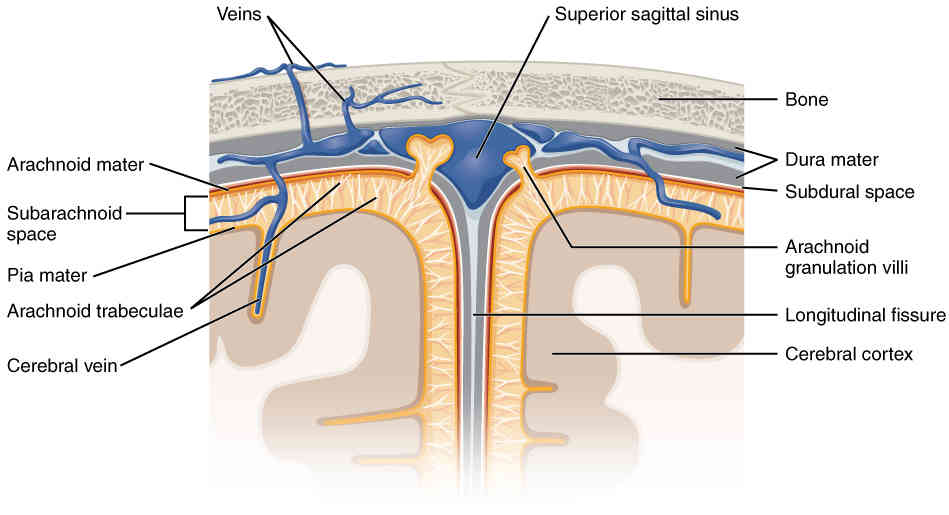

This page is under construction. For now, it is just a resource of the images found in the OpenStax Anatomy and Physiology Handbook. It wil slowly change into a revision tool. Each slide has a number. Use this to refer to the slide. When completed, it will have an unlabelled section, with labelled slides in parallel. On the unlabelled slides, write your answer and use the labelled slide to assess yourself. Keep track by also noting the number on each slide. Improvement at each attempt is important, more so than full marks on a first attempt.